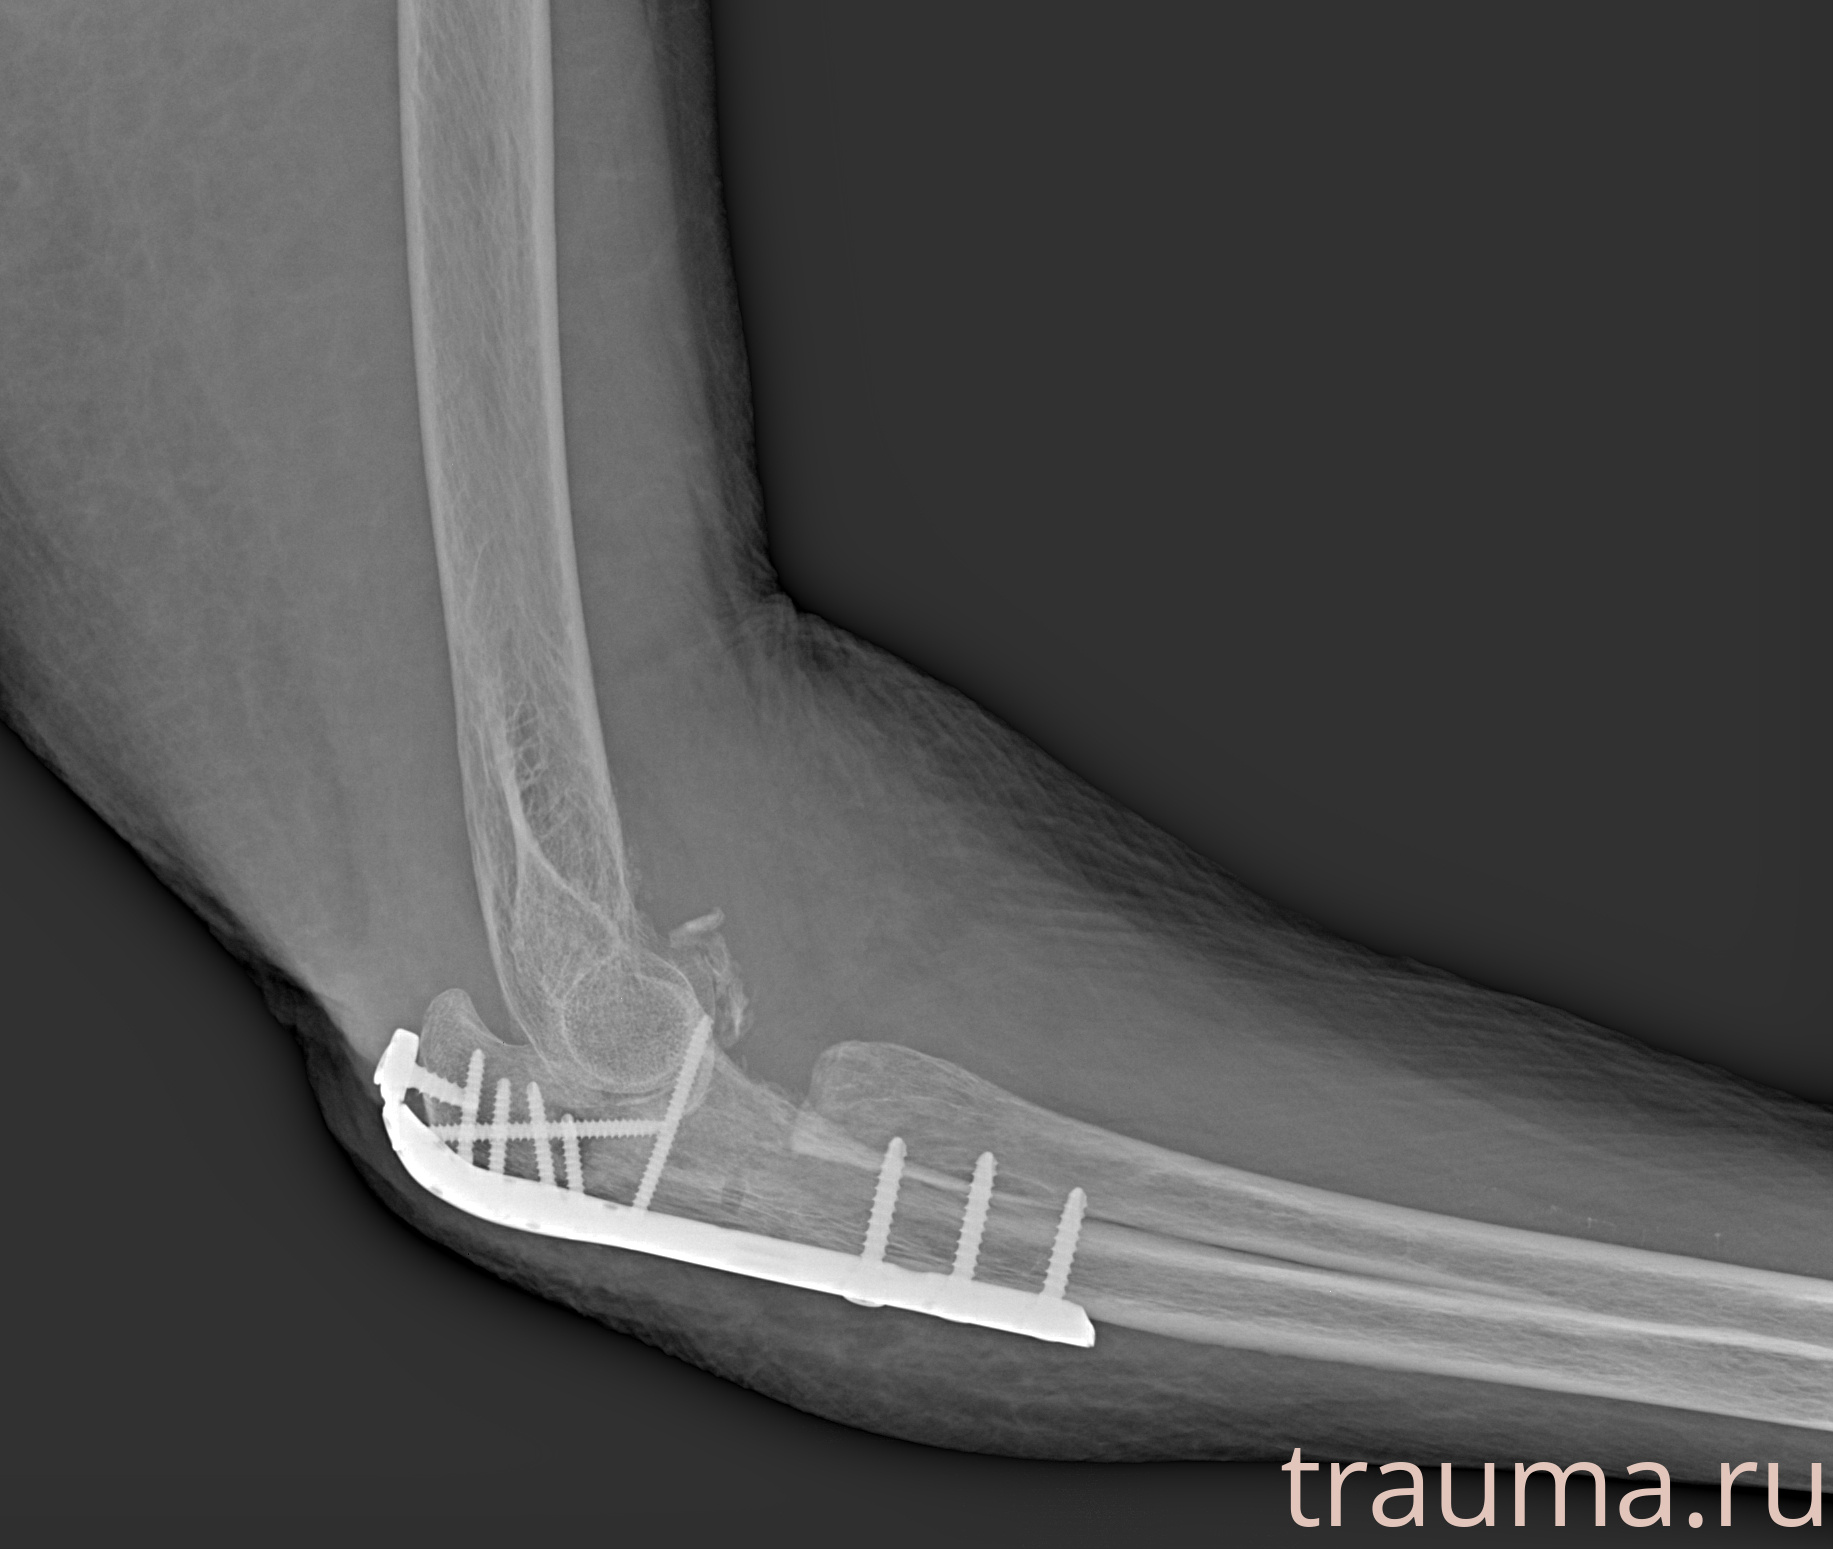

Рентгенограммы